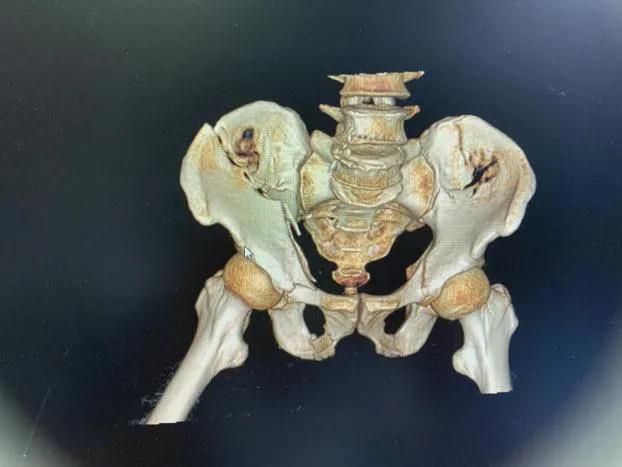

术前影像资料